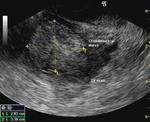

Ultrasound images of carcinoma of endometrium

Transabdominal and transvaginal sonography of the uterus in this postmenopausal patient reveals: 1) Grossly thickened endometrium 2) fine cystic lesions within the endometrial mass 3) invasion of the myometrium by the mass 4) increased vascularity of the lesion on color doppler imaging. These ultrasound images suggest Stage 1B (FIGO) carcinoma of the endometrium. The patient underwent hysterectomy after histopathological study confirmed the presence of malignancy (adenocarcinoma).